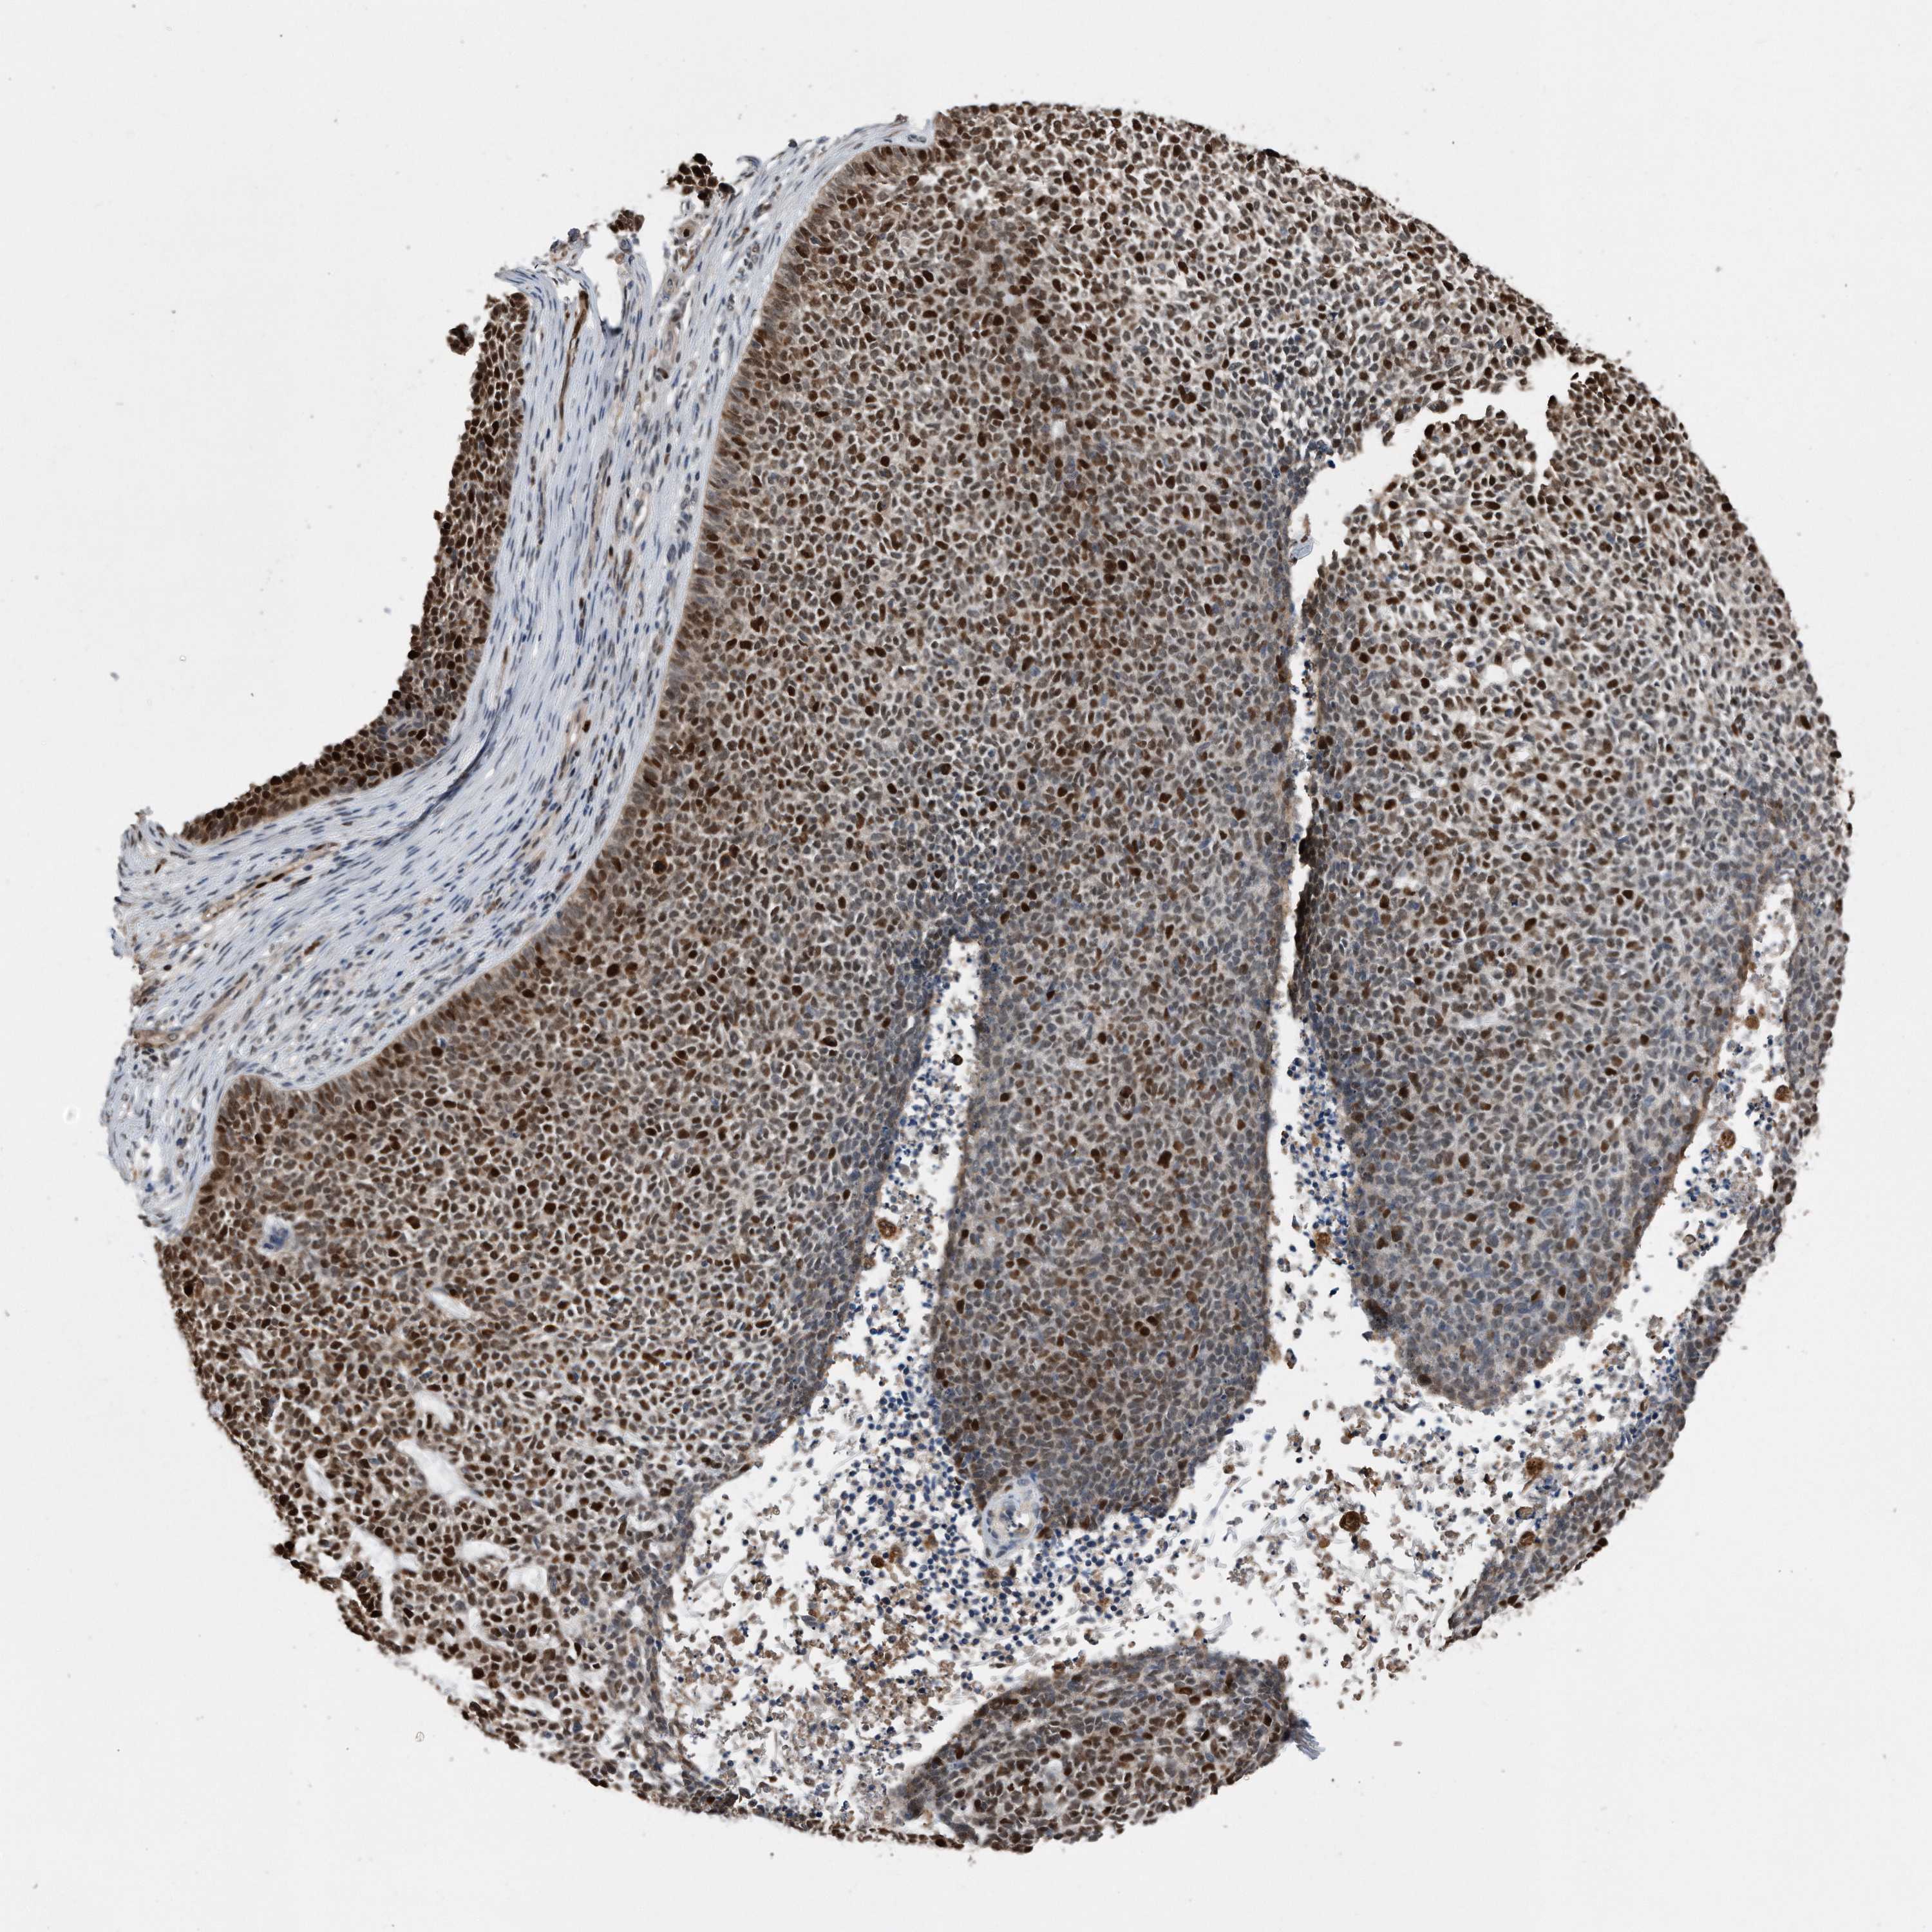

CANCER SKIN CANCER Show tissue menu

Basal cell and squamous cell cancer

SKIN CANCER - Protein expressioni

A mouse-over function shows sample information and annotation data. Click on an image to view it in a full screen mode. Samples can be filtered based on level of antibody staining by selecting one or several of the following categories: high, medium, low and not detected. The assay and annotation is described here.

Each image is clickable and will lead to virtual microscopy that enables deeper exploration of all samples and also displays staining intensity scores, fraction scores and subcellular localization as well as patient and tissue information for each sample.

HPA030521

HPA030522

HPA030523

CAB000148

CAB080240

CAB080241

CAB080242

Staining

High

Medium

Low

Not detected

Intensity

Strong

Moderate

Weak

Negative

Quantity

>75%

75%-25%

<25%

None

Location

Nuclear

Cytoplasmic/membranous

Cytoplasmic/membranous,nuclear

Basal cell carcinoma

Squamous cell carcinoma, NOS

Squamous cell carcinoma, metastatic, NOS